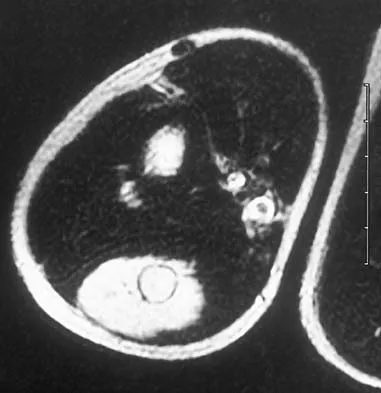

Question 50

Figures 34a through 34c show an axial proton density (spin echo long TR, short TE) image, a sagittal inversion recovery (STIR) image, and a sagittal T1-weighted (short TR, short TE) image of the left thigh. What is the most likely diagnosis?

Explanation